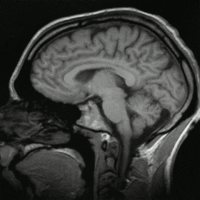

Мозг Homo sapiens

[Править]Мозг

Человек обладает самым развитым мозгом среди животных. Отношение массы мозга к массе тела больше, чем у многих других животных (за исключением, например, мелких птиц[21], коатов или паукообразных обезьян[22]), а абсолютная масса мозга больше лишь у слонов икитообразных[21].

У человека хорошо развиты области мозга, отвечающие за равновесие и координацию движений, что позволяет ходить на двух ногах. Обонятельные области, напротив, развиты слабо, что соответствует чрезвычайно слабому обонянию. С другой стороны, человек, как и все приматы, обладает стереоскопическим зрением.